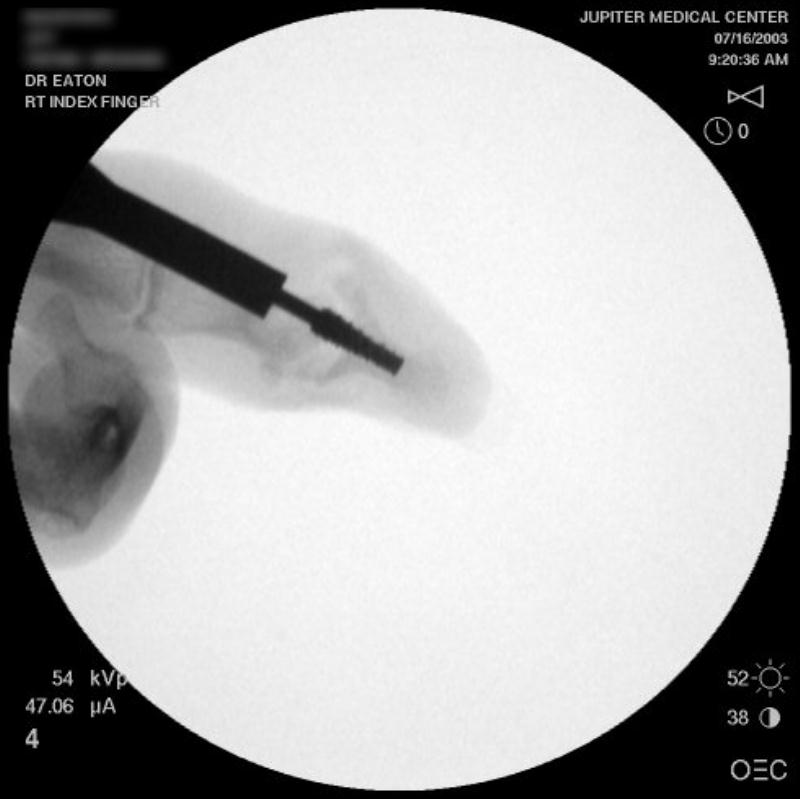

Intraoperative fluoroscopy.

Intraoperative fluoroscopy using the same technique as above. The trial spacers: